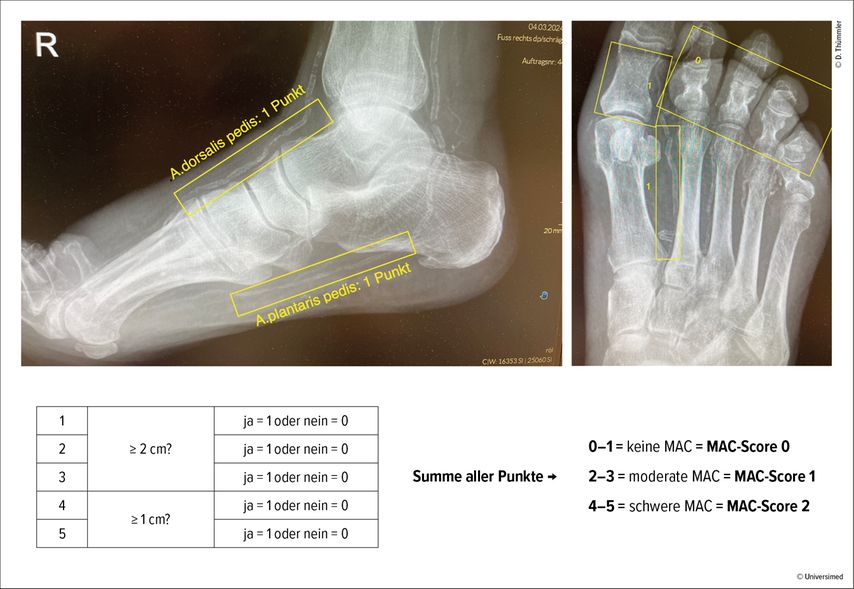

Ferraresi und seine Kollegen haben einen sehr einfach zu erhebenden MAC-Score entwickelt, der dem oben beschriebenen SAD-Score frappierend ähnelt, sowohl in der Erfassung der Schwere der Erkrankung als auch in der davon abzuleitenden Prognose.2,3 Dafür benötigt es lediglich konventionelle Röntgenaufnahmen des Fußes dorsoplantar und seitlich. Es werden 5 Gefäße beurteilt mit der einfachen Frage, ob sie sichtbar sind: und zwar die A.dorsalis pedis und die plantare Arterie im seitlichen Bild und die intermetatarsale Arterie zwischen 1. und 2. Strahl im dorsoplantaren Bild. Wenn diese jeweils auf 2cm Länge verkalkt sind, gibt es dafür jeweils einen Punkt. Es folgen noch eine digitale Arterie am Großzeh (medial oder lateral) und eine beliebige digitale Arterie an den anderen kleinen Zehen – wenn diese auf jeweils 1cm Länge verkalkt zur Darstellung kommen, so gibt es auch dafür je einen Punkt. Die Punkte werde addiert (Abb. 1):

-

0–1 Punkt: MAC-Score 0 (keine MAC)

2–3 Punkte:MAC-Score 1 (moderat)

4–5 Punkte: MAC-Score 2 (schwer)

Diese Röntgenbeurteilung ist einfach durchzuführen und war hoch reproduzierbar zwischen unterschiedlichen Anwendern mit einem hohen Korrelationskoeffizienten (0,96). Die Sensitivität und Spezifität des MAC-Score, um einen SAD-Score vorauszusagen, waren mit 100% respektive 98,1% für SAD0 und SAD2 und mit 99,1% bzw. 92,7% für SAD-1 erstaunlich hoch (Abb. 2).